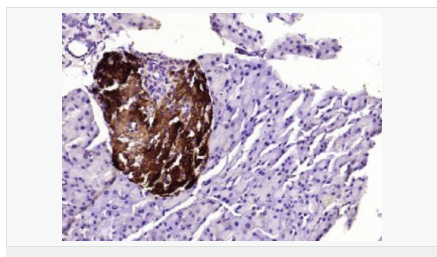

交叉反應:Human,Mouse,Rat(predicted:Pig,Horse,Rabbit) 推薦應用:WB,IHC-P,IHC-F,ICC,IF,ELISA

產品應用WB=1:500-2000 ELISA=1:5000-10000 IHC-P=1:100-500 IHC-F=1:100-500 ICC=1:100-500 IF=1:100-500 (石蠟切片需做抗原修復)